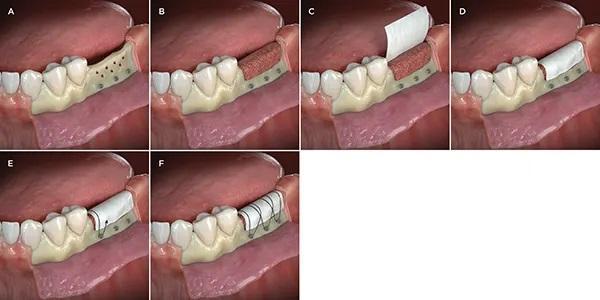

Фото 1: Техника использования винтов для фиксации мембраны в качестве анкеров для стабилизирующих мембрану швов. (A) Полное освобождение лоскута, удаление коркового слоя кости и установка винтов на 3-5 мм за пределы дефекта; обратите внимание, что головки винтов находятся на 0,5-1 мм выше буккального края остаточного гребня. (B) Костный трансплантат, адаптированный к дефекту. (C, D) Резорбируемая мембрана обрезана и подогнана к дефекту. (E) Первоначальный шов, закрепленный вокруг первого винта, наложенный на коллагеновую мембрану и проходящий через небный лоскут изнутри наружу, снова проходящий через небный лоскут снаружи внутрь (от надкостницы к эпителию). (F) Наложение швов, повторяющее процесс вокруг оставшихся винтов для обеспечения стабилизации мембраны.